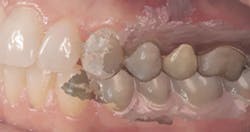

Figures 2 and 3: Additional restorations using Lava Esthetic